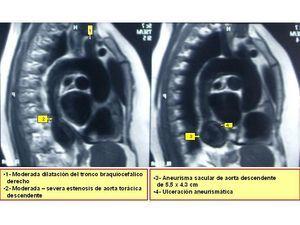

En las pruebas complementarias realizadas destacaba un EKG con trazado en ritmo sinusal con registro electrocardiográfico compatible con hipertrofia de ventrículo izquierdo. Radiografía de Tórax (figura 1) con calcificación del botón aórtico, con imagen indicativa de aneurisma de aorta torácica. Aparato urinario en vacío: se visualizan de forma completa las dos siluetas renales. No se visualizan calcificaciones vasculares. Ecocardiografía: compatible con hipertrofia moderada del ventrículo izquierdo. Ecografía Doppler renal: se observan ambos riñones de configuración normal, riñón derecho de 10,3 cm y riñón izquierdo de 9,4 cm de tamaño, con ecoestructura compatible con la normalidad. Índices de resistencia normales. Imagen ecográfica de dudoso aneurisma tóraco-abdominal.

Debido a los hallazgos radiológicos de aneurisma y asimetría renal leve, solicitamos una angio-TC torácica en la que se evidencia un aneurisma de aorta descendente distal, de tipo sacular, de 4,3 cm de diámetro. Ampliamos estudio con una angio-IRM toráco-abdominal (figura 2, figura 3, figura 4, figura 5) en la que se observan signos de miocarditis. Estenosis en múltiples niveles de la aorta, con signos de inflamación activa y aneurisma focal de aorta torácica descendente. Afectación difusa de aorta abdominal, así como de sus principales ramas viscerales. Triple arteria renal derecha y doble arteria renal izquierda. Estenosis de la arteria polar superior izquierda.

Figura 2. Angio-IRM cardíaca.

Figura 3. Angio-IRM torácica.